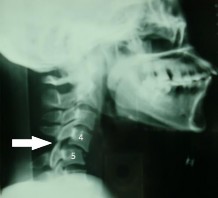

Hình 1.24: Bong gân nặng C5-C6, có đủ năm tiêu chuẩn của René Louis : số 1 là khoảng cách hai mỏm gai tăng bất thường; số 2 là mặt khớp dưới của C5 không song song với mặt khớp C6; số 3 là lộ mặt khớp trên của C6 >50%; số 4 là góc hai cao nguyên sống >100 ; số 5 là trượt C5 ra trước.

Hình 1.25: Bán trật 2 mỏm khớp C4-C5; mũi tên chỉ mỏm khớp dưới của C4 còn nằm trên đỉnh mỏm khớp trên của C5 (kiểu chim đậu).